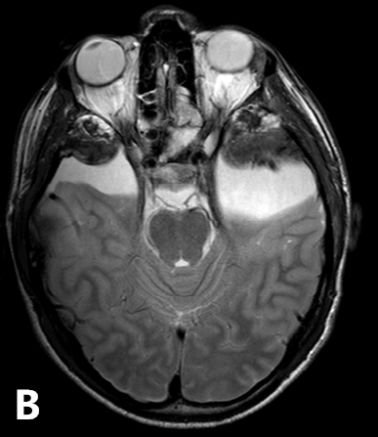

25岁男性患者,有双侧颞部蛛网膜囊肿,因醉驾而发生车祸。入院时GCS评分为15分,体格检查未见阳性体征;头颅CT和MRI提示双侧颞部蛛网膜囊肿的前端各有一颞部硬膜外血肿。左颞蛛网膜囊肿为4.8×5.4cm,右颞囊肿为3.1×3.7cm。左侧颞部EDH最大厚度3cm,右侧2.2cm;同时伴有横向的颞骨骨折(图1)。给予患者保守治疗。随后的CT复查显示EDH稳定(图2)。出院后3周,复查头颅CT显示,EDH明显吸收(图3)。

图3. 3周后头颅CT复查。